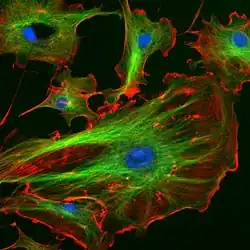

Fluorescentiemicroscopie is een techniek die in biologisch en medisch onderzoek wordt gebruikt waarbij fluorescerende kleurstoffen worden gebruikt die oplichten als ze worden bestraald met licht van een kortere golflengte. De meeste vormen van fluorescentiemicroscopie maken gebruik van sera van kunstmatig geproduceerde antistoffen. De methode wordt dan ook wel immunofluorescentie-, ofwel IF-microscopie genoemd. Deze zijn afkomstig van bijvoorbeeld muizen of ratten, en zijn specifiek gericht tegen een bepaald, bekend eiwit. Als het serum wordt toegevoegd aan een weefsel, zullen de antistoffen binden aan het doeleiwit. Niet-gebonden antistoffen worden weggewassen. De antistoffen zijn voorzien van een fluorescente kleurstof, en daarmee worden ze microscopisch zichtbaar. Er worden polyklonale en monoklonale sera onderscheiden. Monoklonale antistoffen zijn allemaal precies identiek (omdat ze afkomstig zijn van 1 unieke kloon van afweercellen), terwijl polyklonale antistoffen verschillende onderdelen van het eiwit kunnen herkennen.

- Ook in het bloed van patiënten kunnen dergelijke auto-antistoffen aangetoond aanwezig zijn. Deze kunnen aangetoond worden door weefsel van gezonde controles bloot te stellen aan het serum van een patiënt (dat deze antistoffen bevat). Als ze inderdaad binden, kunnen ze gekleurd worden door als tweede stap antistoffen tegen menselijke antistoffen eraan toe te voegen. Door verschillende verdunningen van het patiëntenserum te testen, en te bepalen bij welke verdunning er nog net een signaal te detecteren is, kan een indruk gekregen worden van de hoeveelheid autoantistoffen. Voorbeeld: als een patiënt antinucleaire antistoffen (ANA) in z'n bloed heeft, kunnen deze bepaald worden door een gekweekte epitheelcellen eraan bloot te stellen. De ANA binden dan aan de celkern, wat via fluorescentiemicroscopie wordt zichtbaar gemaakt.